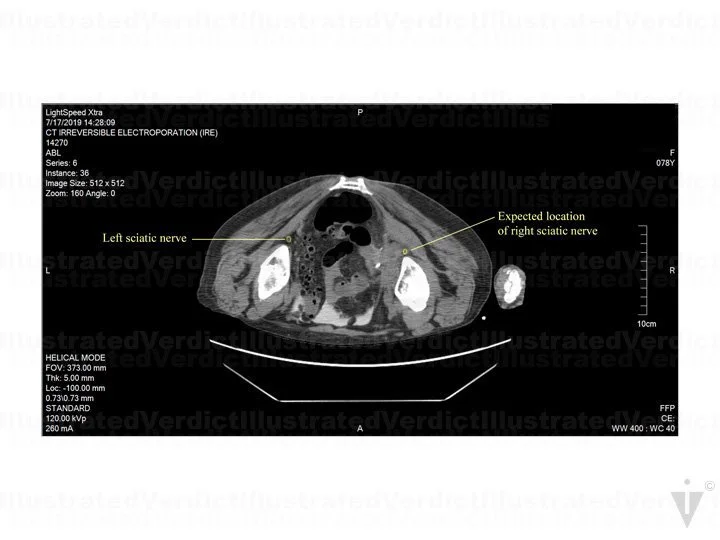

A 78-year-old woman with a history of infiltrating endometriosis presented with persistent, chronic pelvic, back, and flank pain. An MRI revealed a right-sided pelvic endometrioma mass, which encapsulated the right ureter and involved her pelvic nerves. She had a stent placed in the right ureter, and unfortunately, the pain increased. She underwent a CT-guided IRE as treatment. Post treatment, she felt pain in her right foot extending up her calf, and she experienced limited feeling in her right toes, foot, or ankle. A month after the procedure, her right pelvic, back, and flank pain had resolved, but she continued to have right leg paresthesia (pins and needles with numbing sensation). Unfortunately, nerve damage was a risk of the procedure. The jury found in favor of the defense.